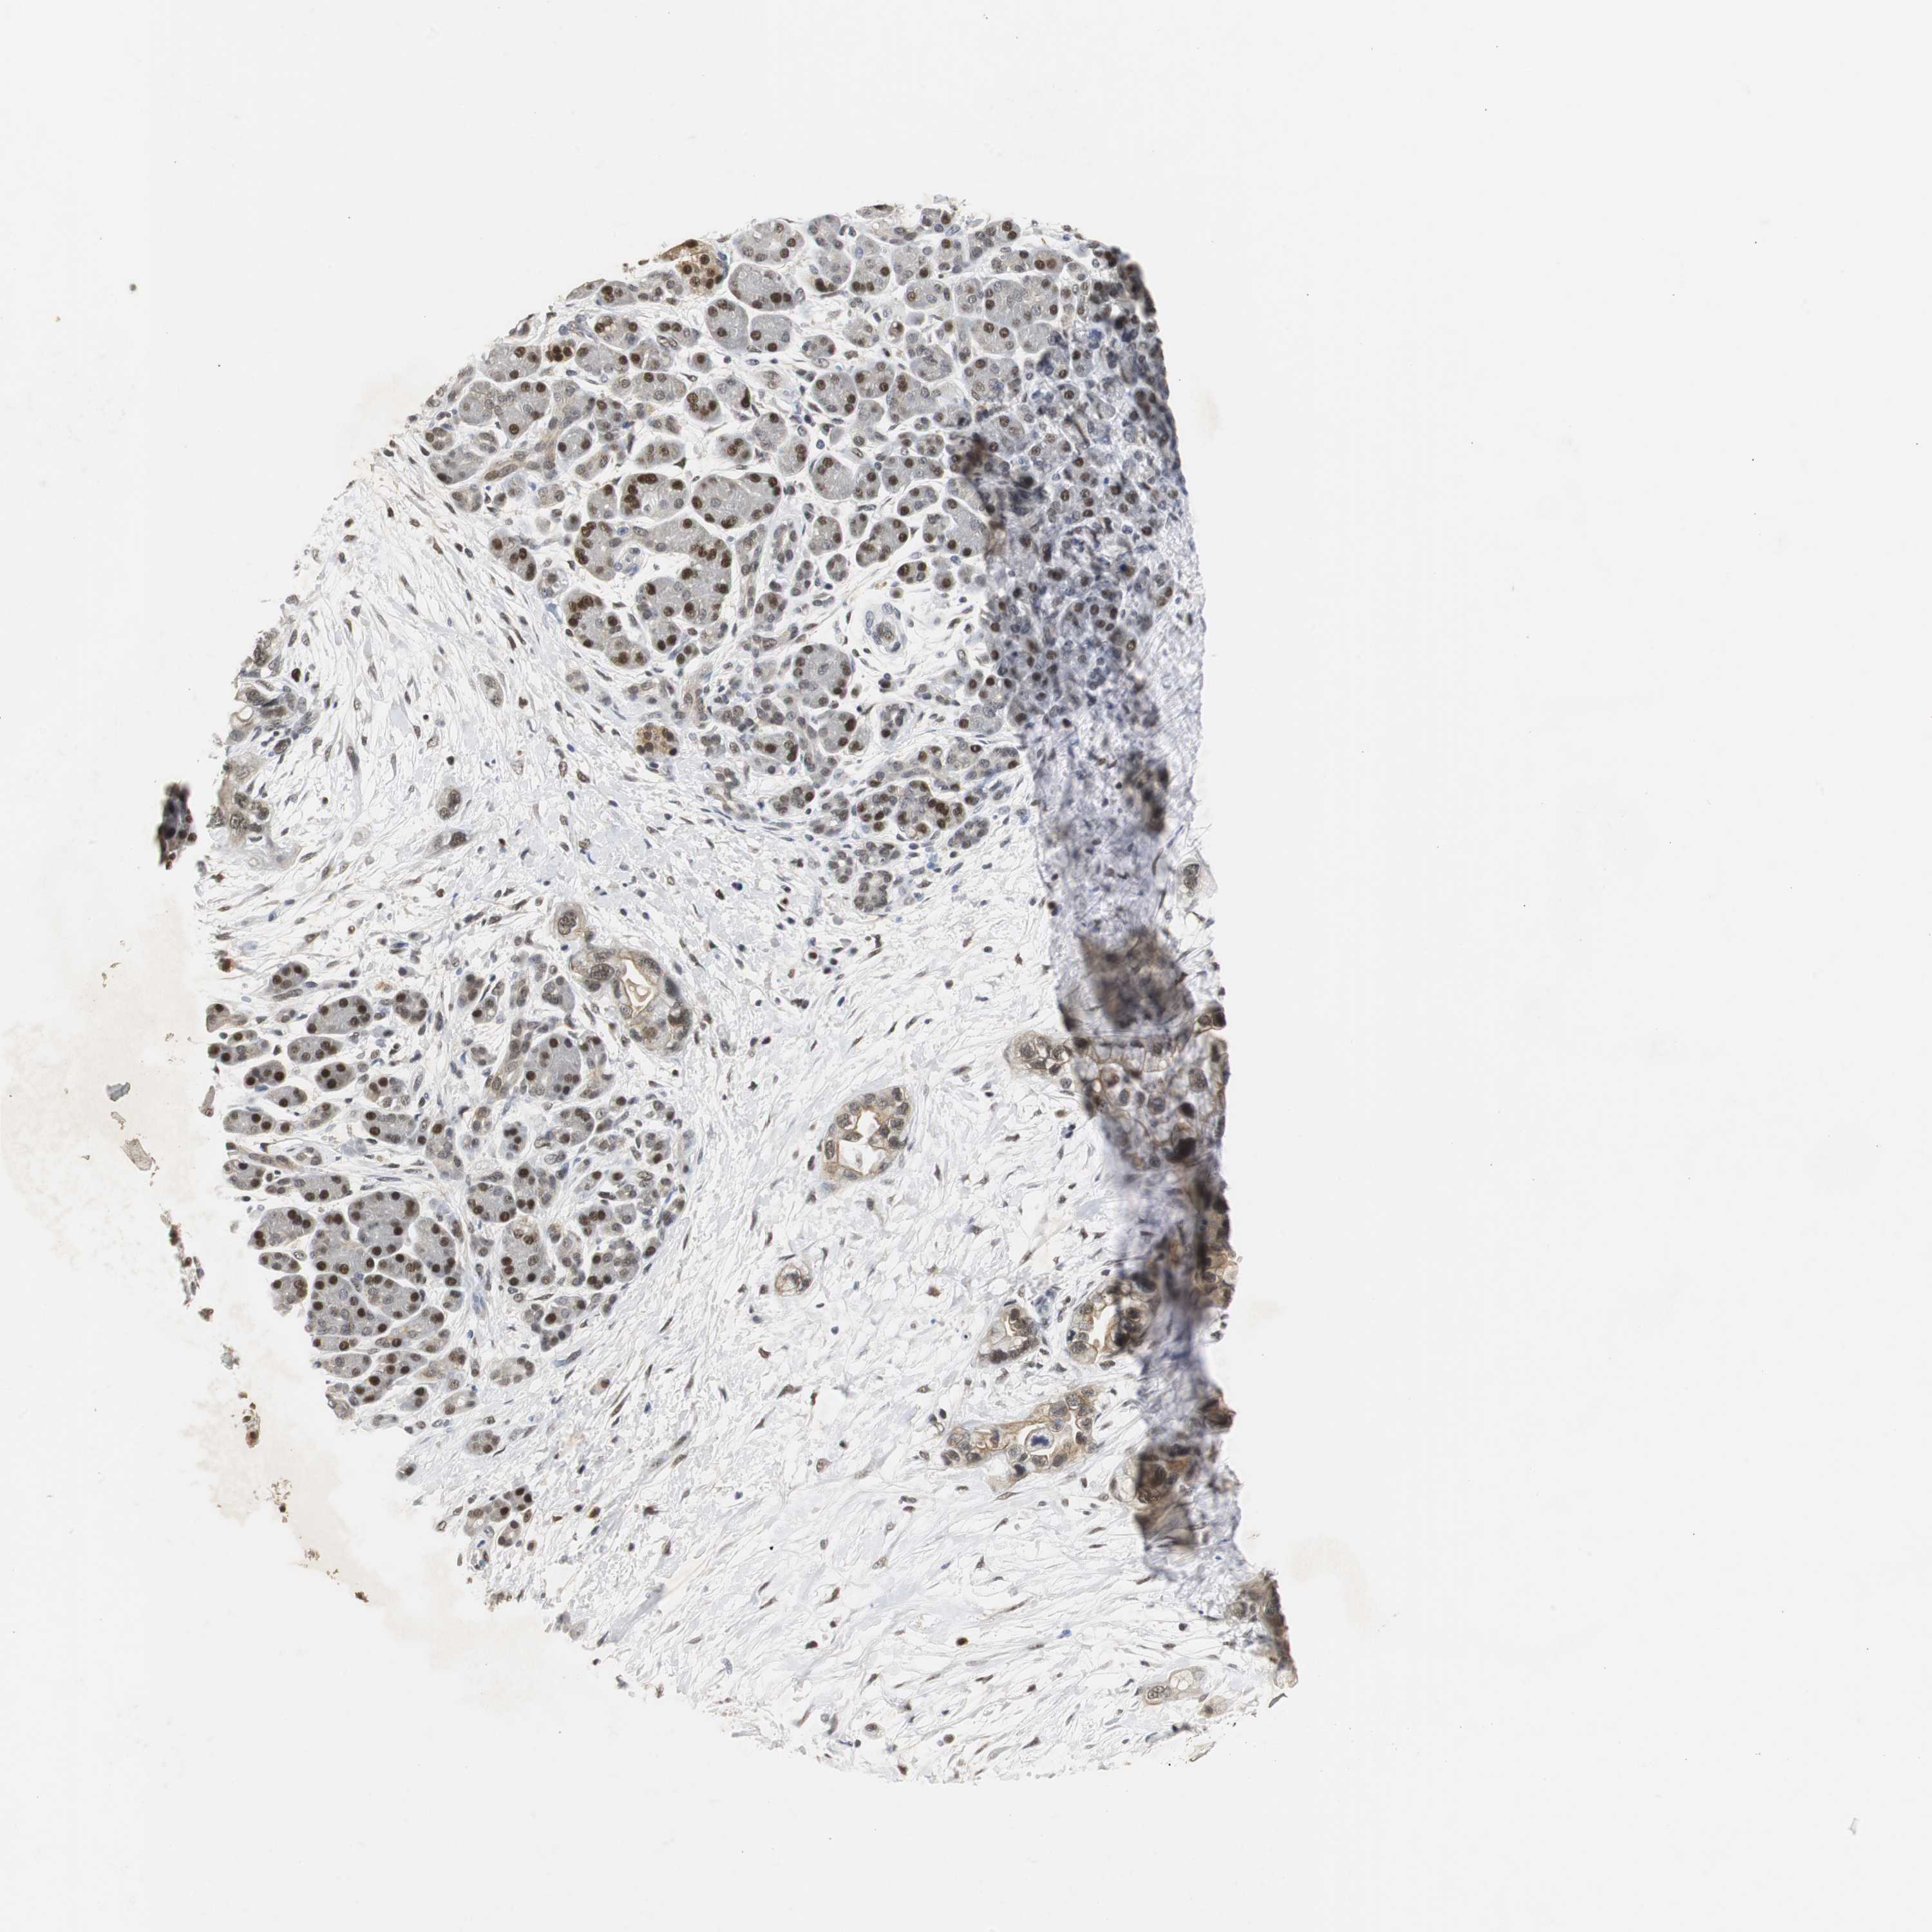

PANCREATIC CANCER - Protein expressioni

A mouse-over function shows sample information and annotation data. Click on an image to view it in a full screen mode. Samples can be filtered based on level of antibody staining by selecting one or several of the following categories: high, medium, low and not detected. The assay and annotation is described here.

Note that samples used for immunohistochemistry by the Human Protein Atlas do not correspond to samples in the TCGA dataset.

Antibody stainingi

Antibody staining in the annotated cell types in the current human tissue is reported as not detected, low, medium, or high, based on conventional immunohistochemistry profiling in selected tissues. This score is based on the combination of the staining intensity and fraction of stained cells.

Each image is clickable and will lead to virtual microscopy that enables deeper exploration of all samples and also displays staining intensity scores, fraction scores and subcellular localization as well as patient and tissue information for each sample.

Antibody HPA007072

Antibody HPA007151

Adenocarcinoma, metastatic, NOS